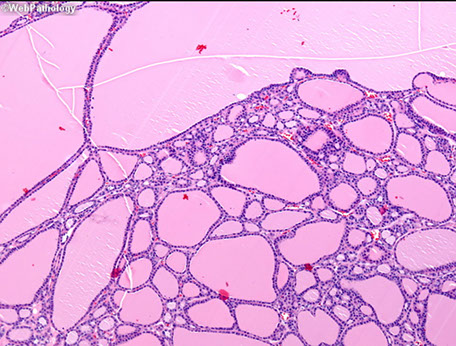

Thyroid consists of lots of follicles / acini, which are made of follicular epithelium with follicular cells and scattered (~1/10) C / parafollicular cells and have thyroglobulin-rich colloid in the center and a thin fibrous capsules goes in and breaks the gland into lobules

Follicular cells: low, simple cuboidal (not very active) to columnar (if more active) epithelium c little stroma c lots of vessels

Follicles are bigger with lots of colloid with dietary iodide deficiency, making the gland hypoactive

- the follicular epithelium is more columnar when active and follicular cells can have colloid droplets inside and form apical pseudopodia c microvilli

Colloid (made of thyrogluobulin, which stores inactive T3 and T4) can look amphophilic or basophilic, this is a normal variant

Colloid nodule

Hyperplastic nodule c big distended follicules

- area of colloid is much greater than the area occupied by the follicular cells